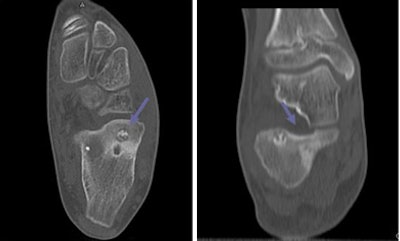

In an example of a 6-year-old with congenital cholesteatoma, thin-section axial images (0.5-mm collimation) were acquired at 100 kVp and 100 mAs, and viewed on isovoxel coronal reconstructions.

| Axial (left) and coronal (right) images of a 6-year-old with congenital cholesteatoma were acquired on a 16-slice MDCT scanner (Aquilion, Toshiba America Medical Systems, Tustin, CA) examined using isovoxel coronal reconstructions. All images courtesy of Dr. S. Bruce Greenberg. |